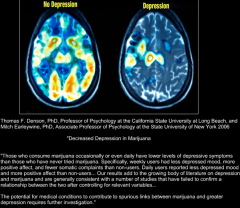

Deprese

B9L0F3OCMAAHcvb.png

B9L0F3OCMAAHcvb.png [ 360.57 KiB | Zobrazeno 52434 krát ]